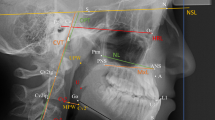

Intra-oral functional compartments have been mentioned in the literature for more than 50 years. In 1953, Eckert-Möbius [21], based on the publication of Noltemeier [22] and proposals of Körbitz published in 1914 [23], described two different functional ‘suction spaces’, one of them around the dental arches (the later inter-occlusal space of Fränkel [24]) and the other below the palatal vault. The formation of a negative pressure at the palatal vault was later confirmed by Fröhlich et al. [25]. Engelke [26] systematically depicted orofacial biofunctional compartments as part of a comprehensive biofunctional model. Biofunctional compartments are spaces formed during particular biological functions, such as deglutition, speech production and respiratory posture: inter-occlusal space (IOS), sub-palatal space (SPS), mid-pharyngeal space and the naso-epipharyngeal space (Fig. 2).

Biofunctional compartment model of the orofacial system (see Engelke [10]): closure of the lips and placement of the tongue at the hard palate form the inter-occlusal compartment (IOS, 1). Contacting of posterior tongue and soft palate supports closure of the sub-palatal compartment (SPS, 2), whereas the tongue and hard palate contact area separates both compartments 1 and 2. The upper airway in conjunction with the velopharyngeal sphincter as borderline forms two further biofunctional compartments (3 and 4)